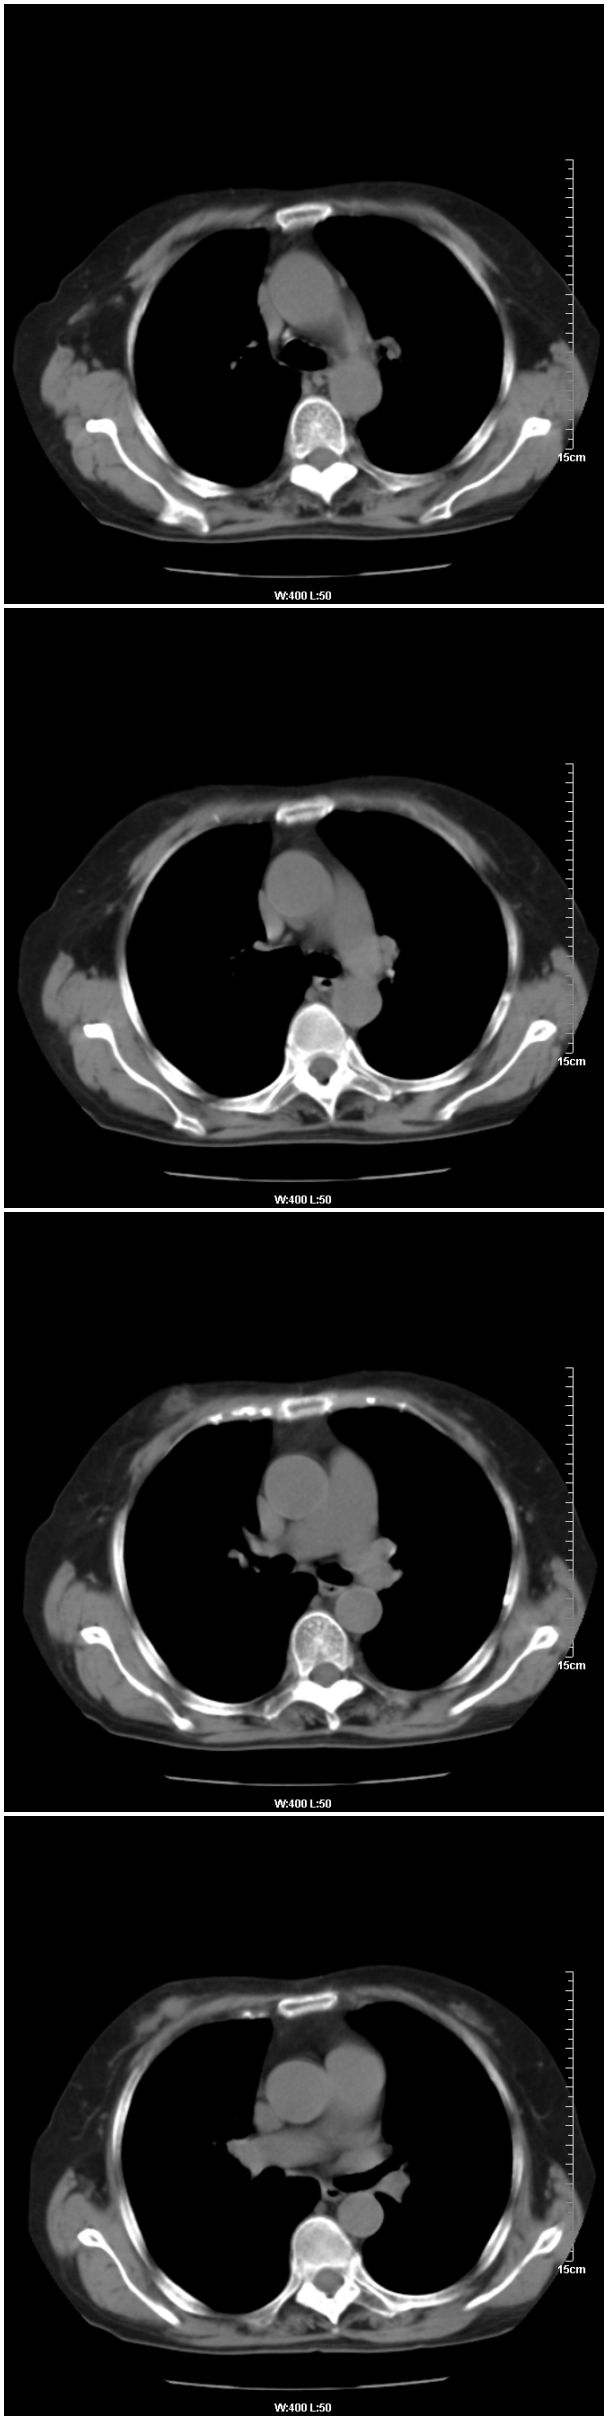

女性,78岁。术前体检发现肺部病变,看看还有什么问题?肺病变是什么性质?

本例临床是以乳腺癌的术前检查平片发现肺部病变的,请战友们看乳腺病变是否能够看出来,在哪一侧?

在右侧,支持!右肺中心型肺癌! 右乳腺肿物。

支持!右肺中叶中心型肺癌!右侧乳腺内上象限结节,建议薄扫

乳腺病变在右侧,右肺门区新生物伴右中叶阻塞性肺炎、部分部张

右肺中叶不规则肿块,管腔阻塞,心包内少量积液,支持右肺中心型肺癌。

应该是右肺中心型肺癌,乳腺的肿物应该在右侧,看见右侧有结节,并乳头凹陷

右侧乳腺内上象限结节影,边缘模糊,右肺病变相邻支气管内见软组织密度影及斑点样钙化灶,考虑肺癌可能性大,建议结合纤支镜检查。

右肺中央型肺癌伴中叶肺不张。

右乳腺内结节病灶,如增强扫描动脉期结节呈明显强化可考虑乳癌。